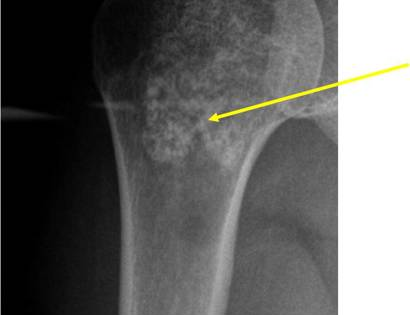

Radiographic imaging is used to help form a diagnosis. These include X-Ray, MRI, CT and Bone Scans.

An example of an enchondroma X-Ray is shown.